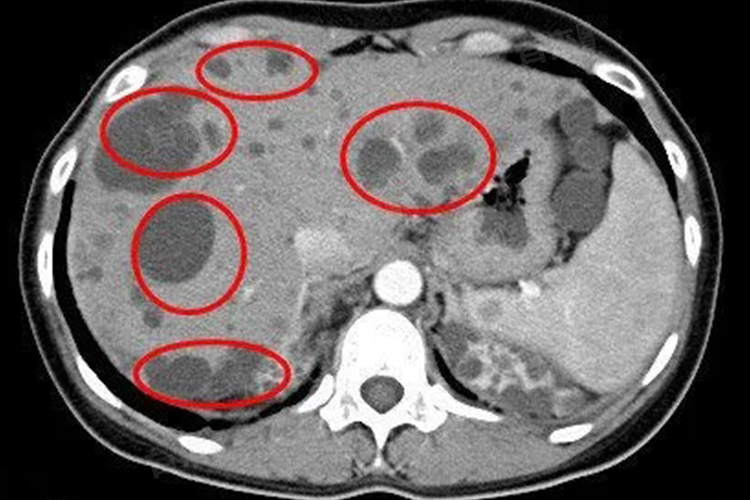

- 肝内多发囊性灶通常是指在肝脏内发现多个充满液体的囊腔,这些囊性灶可能由多种原因引起。其中,最常见的是肝囊肿。肝囊肿大多为先天性,是由于胚胎时期胆管发育异常所致。一些寄生虫感染,如肝包虫病,以及创伤后形成的假性囊肿等也可能表现为肝内多发囊性灶。

- 如果肝内多发囊性灶较小,且患者没有任何症状,一般不需要特殊治疗。这种情况下,可以定期进行超声、CT等影像学检查,观察囊性灶的大小、数量变化以及有无其他异常表现。通常建议每半年至一年复查一次,以便及时发现可能出现的问题。

- 但是,如果囊性灶较大,可能会产生一些不良影响,此时可能需要考虑治疗。例如,当囊肿增大压迫周围组织和器官时,可能会引起右上腹疼痛、腹胀、恶心、呕吐等不适症状。巨大的囊肿还可能压迫胆管,导致胆汁排泄不畅,出现黄疸。